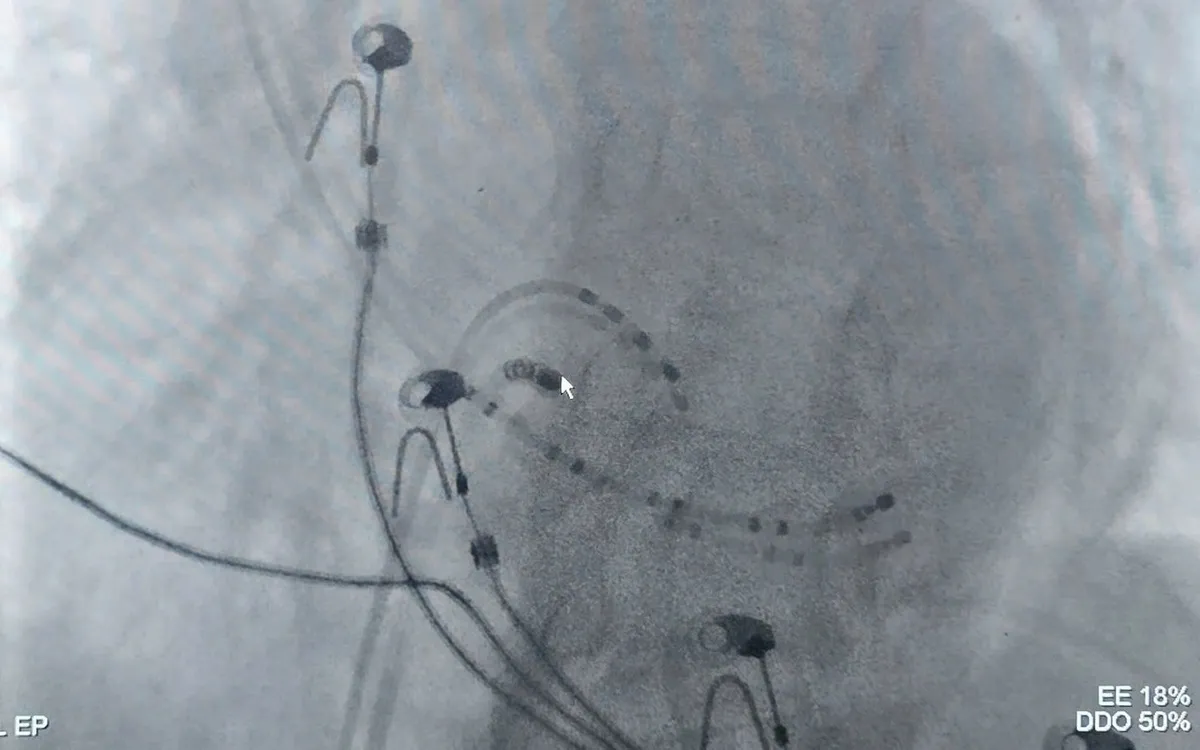

Nhận định nguy cơ tái phát cao, bệnh nhân được chuyển đến Bệnh viện Đa khoa tỉnh Quảng Ninh để điều trị chuyên sâu. Tại đây, các bác sĩ tiến hành thăm dò điện sinh lý và đốt triệt ổ rối loạn nhịp bằng sóng cao tần. Thủ thuật diễn ra an toàn, không biến chứng, nhịp tim duy trì ổn định.